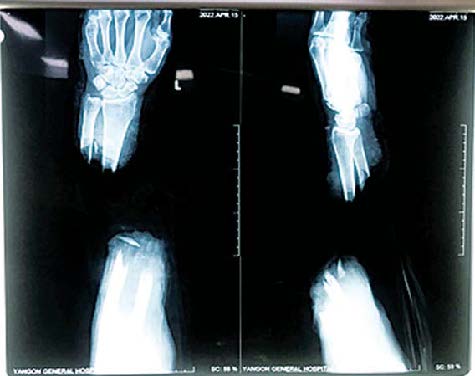

ရန်ကုန်ပြည်သူ့ဆေးရုံကြီး၌ ဧပြီ ၁၄ ရက်တွင် လက်ကောက်ဝတ်အထက်မှ ပြတ်တောက်သွား သောလက်အား ပြန်လည်ဆက်ပေးသည့် ခွဲစိတ်ကုသမှုကို အောင်မြင်စွာ ဆောင်ရွက်ပေးနိုင်ခဲ့ကြောင်း သိရသည်။

ခွဲစိတ်ကုသမှုကို ရန်ကုန် ပြည်သူ့ဆေးရုံကြီးမှ လက်ပိုင်း ဆိုင်ရာခွဲစိတ်ကုသမှု ပါရဂူဘွဲ့ သင်တန်းသား ဒေါက်တာဖြိုးမောင်မောင် ဦးဆောင်သည့် လက်ထောက် ဆရာဝန်(အရိုး) ဒေါက်တာမောင်မောင်လွင်၊ ဆေးပညာဘွဲ့လွန် (အရိုး) သင်တန်းသား ဒေါက်တာမင်းသူ၊ ဒေါက်တာဟိန်းပြည့်အောင်၊ မေ့ဆေးအထူးကုဆရာဝန် ဒေါက်တာထွန်းထွန်းနိုင်နှင့် အထက်တန်းသူနာပြု ဒေါ်မေသူရတို့ ပါဝင်သောအဖွဲ့က ဧပြီ ၁၄ ရက် ည ၇နာရီ မိနစ် ၅၀ မှ စတင်ဆောင်ရွက်ခဲ့ရာ ဧပြီ ၁၅ ရက် နံနက် ၁ နာရီခွဲတွင် ခွဲစိတ်ကုသမှုပြီးဆုံးခဲ့ကြောင်း သိရ သည်။

အဆိုပါ လူနာ၏ လက်မှာ ခွဲစိတ်ပြီးချိန်မှစတင်၍ သွေးကြောများ ဖြည်းဖြည်းချင်း ပြန်လည် လှည့်ပတ်စီးဆင်းလာပြီး ဧပြီ ၂၅ ရက်မှစတင်၍ အကြောအဆစ် ရောဂါကု ပညာဌာန ပြင်ပလူနာဌာနတွင် လေ့ကျင့်ခန်းများ လုပ်ဆောင်ခဲ့ပြီး ဧပြီ ၂၉ ရက်တွင် ဆေးရုံမှ ဆင်းခွင့်ပြုပြီးဖြစ်သည်။